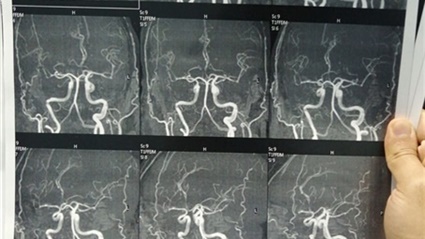

وأكد الدكتور عزيز، رئيس الجامعة أن فريقا طبيا بقسم جراحة المخ والأعصاب، تمكن من إجراء قسطرة تشخيصية لثلاث حالات تعاني من نزيف حاد بالمخ وغيبوبة عميقة، حيث تم إجراء التدخلات الجراحية العاجلة لاستعادة الوعي، وبعد تحسن الحالات خضعت للعديد من الفحوصات الطبية اللازمة لتشخيص أسباب النزيف، وعلى رأسها القسطرة التشخيصية لشرايين وأوردة المخ.

وأوضح الدكتور حسان النعماني، عميد كلية الطب البشري أن نتائج القسطرة أسفرت عن تشخيص تمدد شرياني بأحد شرايين المخ ووحمة دموية داخل أنسجة المخ للمريض الثاني، إضافة إلى وجود ورم دموي خبيث بقاع المخ للمريض الثالث، مشيراً إلى أن قسم جراحة المخ والأعصاب يقدم تلك الخدمة الطبية منذ عام ٢٠٠٩م، حيث تم إجراء ما يقرب من عمل ٢١٥ حالة قسطرة تشخيصية، وعلاج أكثر من ٧٠ حالة مرضية.